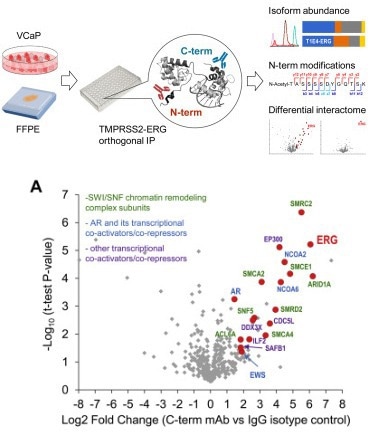

Products from Sino Biological are regularly mentioned in reputable journals, indicating their critical role in KLK-related research. These products facilitate research activities like ELISA assays, isozyme mapping, and the detection of highly expressed Kallikreins, particularly carcinomas. To support the development of more precise prostate cancer diagnostics, Fu et al. employed anti-KLK3 rabbit monoclonal antibody (Sino Biological) as an IgG control isotype in the isoform mapping and interactome studies of endogenous TMPRSSS2-ERG fusion protein in VCaP prostate cancer cells by orthogonal immunoprecipitation-mass spectrometry assays.

For the interactome studies, antibody isotype controls included anti-KLK3 rabbit monoclonal antibody (Sino Biological) as an IgG isotype control for EPR3864(2) antibody in the mass-spectrometric analysis. Image Credit: https://doi.org/10.1016/j.mcpro.2021.100075